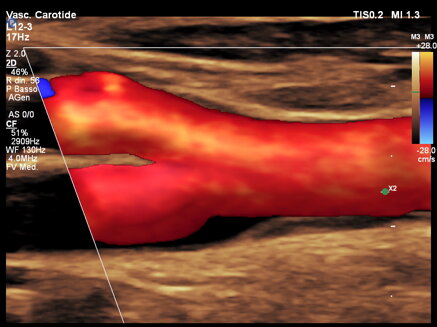

L’ecocolordoppler dei tronchi sovraortici (TSA) è un esame che permette di studiare la morfologia dei vasi, riconoscere le lesioni aterosclerotiche (placche) e la loro gravità. L’ecocolordoppler fornisce immagini a colori (rosso e blu) dei flussi venosi e arteriosi evidenziando anche le più piccole lesioni delle pareti dei vasi consentendo di valutarne con precisione l’entità. L’ecocolordoppler dei tronchi sovraortici viene richiesto per l’inquadramento di un paziente a seguito di un attacco ischemico cerebrale per la diagnosi di aneurisma e per lo studio della arterie in pazienti con fattori di rischio cardiovascolare quali ipertensione arteriosa, ipercolesterolemia, fumo, ecc.